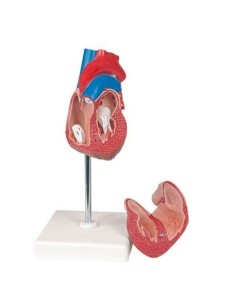

Dal cranio in 22 parti con incastri magnetici ai modelli di colonna vertebrale, da quelli di articolazioni a quelli di cuore, ogni pezzo della nostra collezione è progettato per un’immersione totale nello studio dell’anatomia umana. I nostri modelli, realizzati tramite scansioni di ossa vere, garantiscono un’esperienza tattile autentica e una fedeltà di peso quasi identica agli originali.